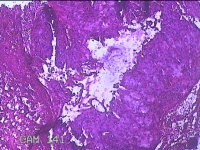

右卵巢黄体囊肿

性别

女

年龄

41岁

临床诊断

右卵巢黄体囊肿破裂

一般病史

下腹痛3小时。

标本名称

大体所见

灰白暗红色囊性肿物2x0.8x0.7cm一个,表面糜烂,切开肿物,内见大量凝血块,囊壁厚约0.1cm。

有点像。不过片子这个效果,没有足够的勇气来诊断。